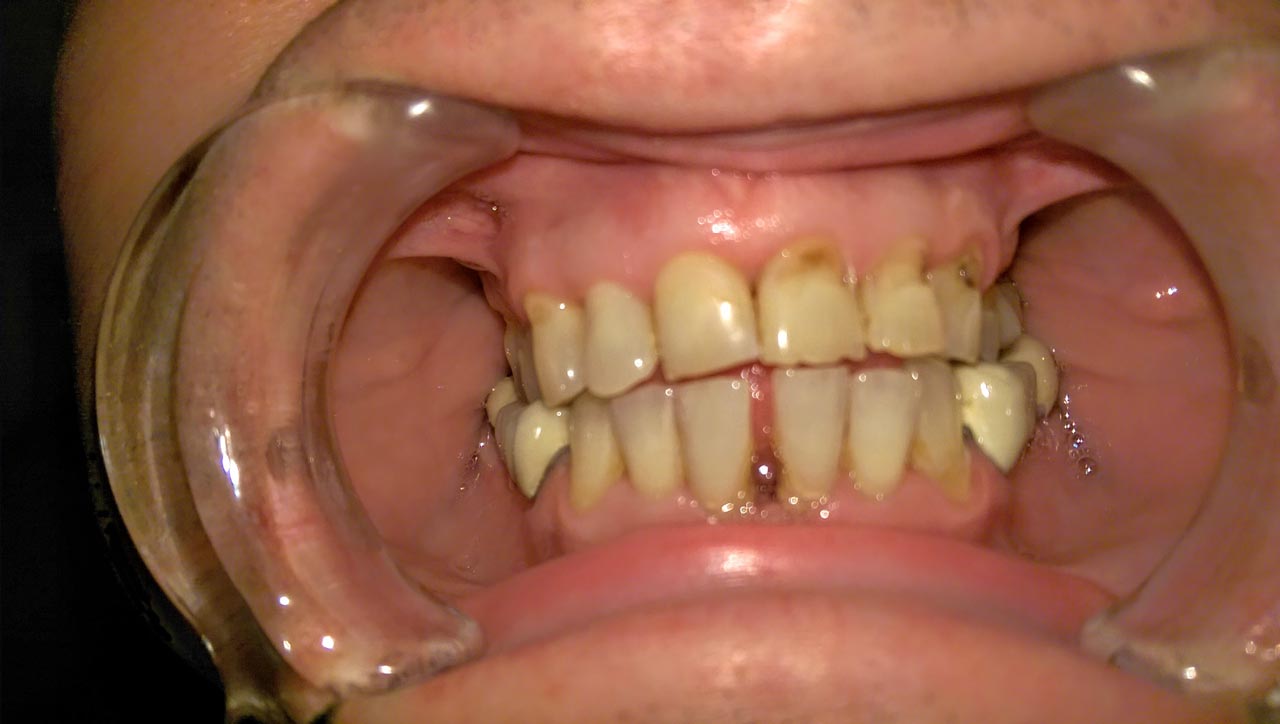

Fogmegtartó kezelések

Betegeink többféle (kémiai kötésű és fényre kötő) esztétikus tömés közül orvosainkkal együtt választják ki a megfelelőbbet! Fémmentes betéteinkkel, koronáinkkal természethűen tudjuk visszaállítani fogazatát. Gyökérkezeléseket csúcstechnológiás gépi tágítóval végezzük, aminek segítségével milliméter pontosan tudjuk bemérni a gyökértöméshez a csatorna hosszát.